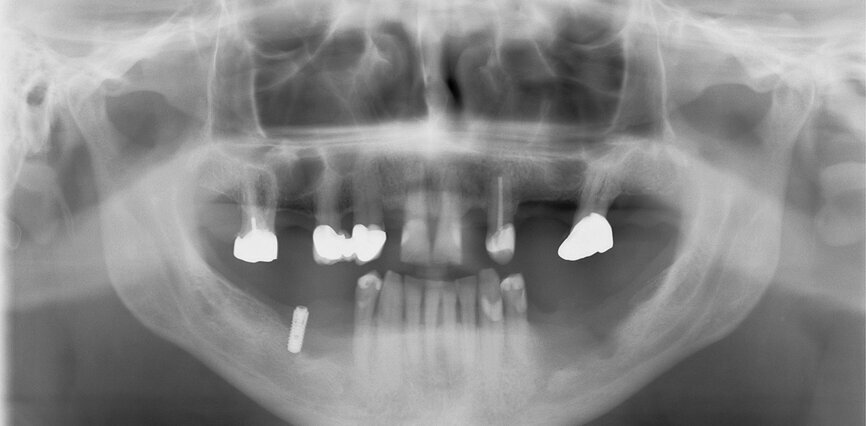

Fig. 1: Initial situation: severe bone defects and implant in situ.

The first was a 51-year-old patient who smoked 30 cigarettes per day and suffered from diabetes and stress (Figs. 1–8). The second was a 76-year-old male patient in good physical condition who smoked 40 cigarettes per day. He underwent reconstruction of the premaxilla (Figs. 9–13). The third was a healthy female patient of 24 years of age who smoked 20 cigarettes per day. She required a sinus lift in region #25 (Figs. 14–21). The patients were informed of the intended process in detail and signed the surgical protocol containing information concerning possible risks of failure and complications, as well as information on the alloplastic and synthetic materials to be used.